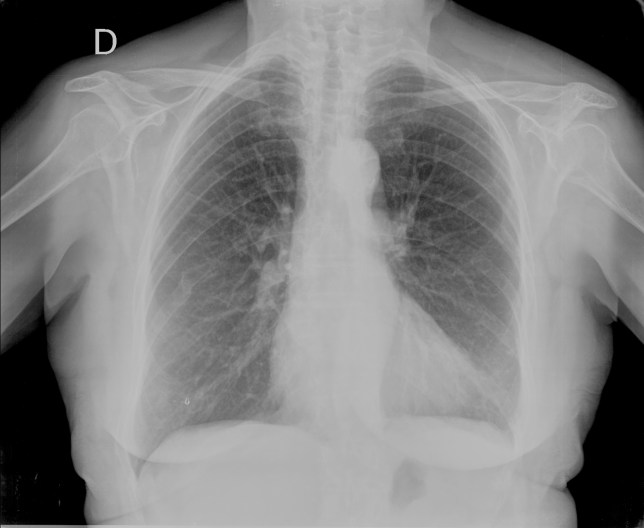

Empecemos, ¿qué ves?

- Comprobar que la placa está bien centrada e inspirada (6 arcos costales anteriores ó 9 posteriores).

- Abdomen y Diafragma

- Partes blandas y estructura ósea.

- Mediastino con silueta cardiaca.

- Parénquimas pulmonares (por separado)

- Comparar un pulmón con otro.

Seguir esta sistemática, dejando el pulmón para el final no nos olvidaremos de lo más importante.

Regla: Acaso Tiene Mucha Patología Pulmonar (Abdomen, Tejidos blandos y hueso, Mediastino, Pulmón por separado, Pulmón bilateral)

Nota: ¡¡¡No olvidar la placa lateral!!! La regla a seguir es la misma. Leer abdomen y diafragma, examinar parte posterior, tejidos blandos y subir por la columna; tráquea y descender por mediastino. Finalmente pulmones.

Solución: Es un estudio Normal. Silueta cardiomediastínica y parénquimas pulmonares sin alteraciones significativas.